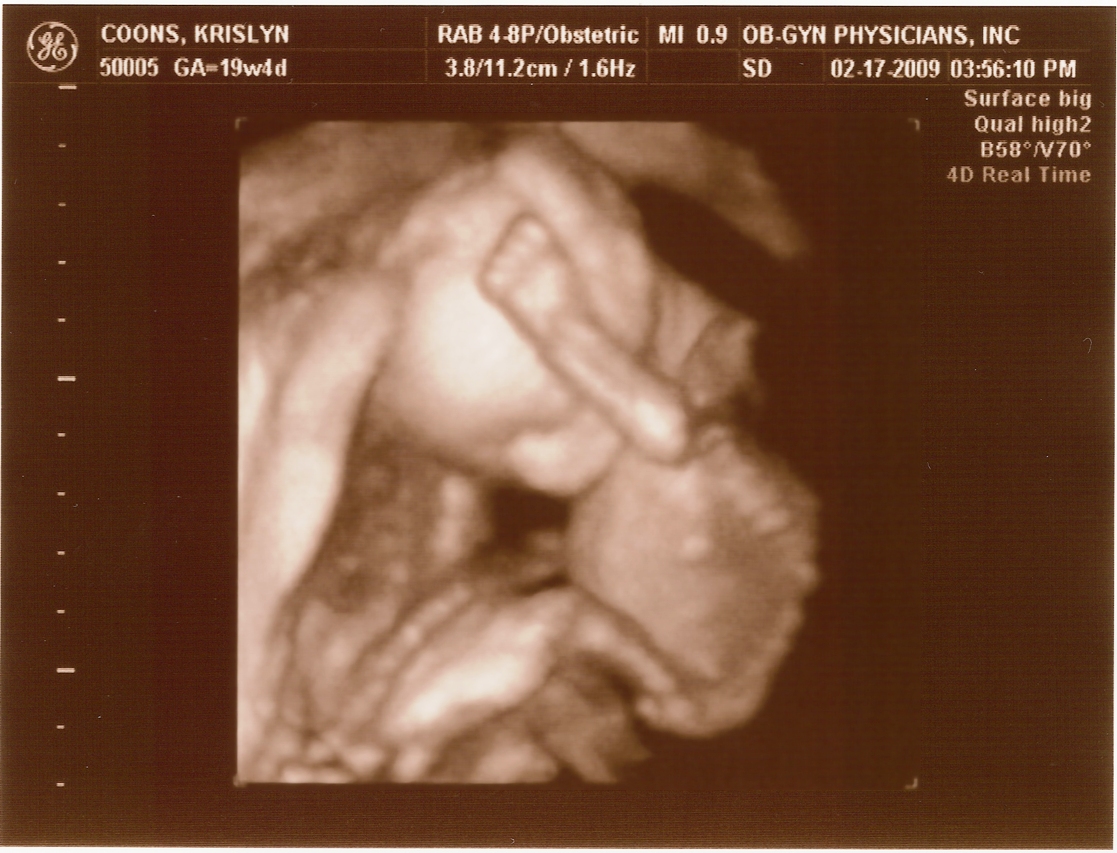

2.17.2009

First ultrasound! The baby measures right on target and appears to be developing normally. All looked and sounded great. Krislyn is finally gaining some baby weight too!